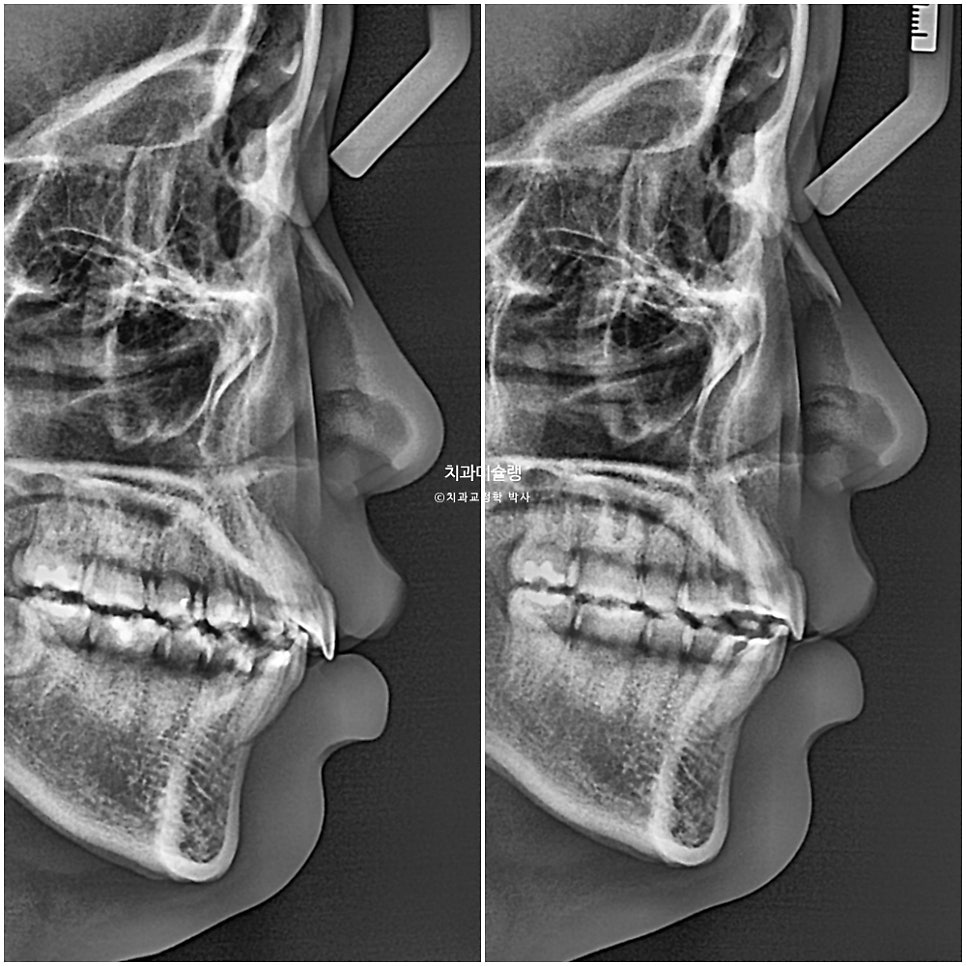

교정 전후 옆 엑스레이 중첩입니다.

앞니 돌출이 해소되며 입술이 한결 편하게 다물립니다.

뒤로 밀렸던 턱이

과개교합이 해소되면서 소량 앞으로 나왔습니다.